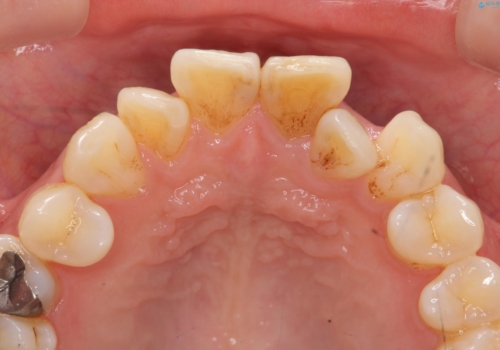

歯の変色 前歯の審美改善

- 前歯の変色の改善を求めて来院されました。

X線写真より、以前に神経の治療が為され変色をきたしている状態であることがわかりました。

根管内の感染は認められないのでセワミッククラウンの製作・装着を行い審美性を改善します。